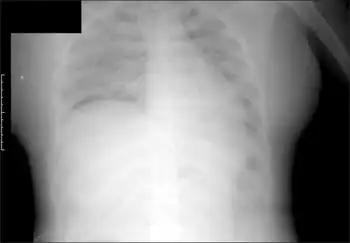

Systemic capillary leak syndrome under general anesthesia-Post operative chest radiography shows pulmonary edema bilaterally